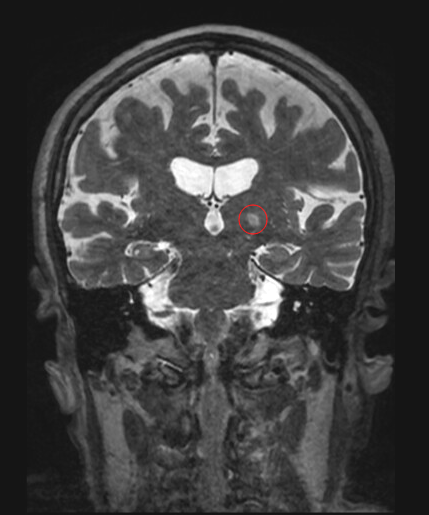

임상, 생리학적, 영상 연구는 소뇌 및/또는 소뇌시상피질 회로의 관련성을 시사한다.[49] 전통적인 올리브 가설은 하올리브 핵의 비정상적인 전기적 활동이 본태성 진전을 유발한다고 제안했지만,[50] 최근 연구들은 소뇌에 초점을 맞춘 신경퇴행성 질환일 가능성을 제시한다.[58]

일부 사례에서는 청반에 루이 소체가 발견되기도 한다.[52][53][54] 파킨슨병으로 진행되는 본태성 진전 환자는 소뇌 문제의 가능성이 낮다.[55] 최근 신경 영상 연구는 본태성 진전에서 전반적인 뇌 기능 네트워크 효율성이 파괴되었음을 시사한다.[56]